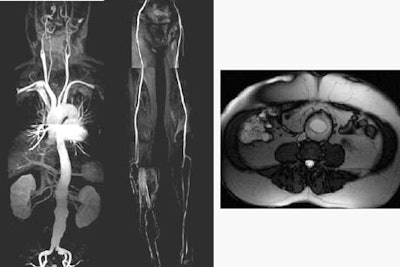

| AngioSURF whole-body 3D MRA consists of five 3-D datasets acquired over 12 seconds each. Total acquisition time of 72 seconds includes 5 12-second acquisitions, with 3-second manual table repositioning between acquisitions. Total coverage is 180 cm from the supraaortic arteries to the runoff vessels. Above, whole-body MRA reveals an unsuspected infrarenal abdominal aortic aneurysm (maximum diameter 5.3 cm) in a 63-year-old male patient. Images courtesy of Dr. Mathias Goyen. |